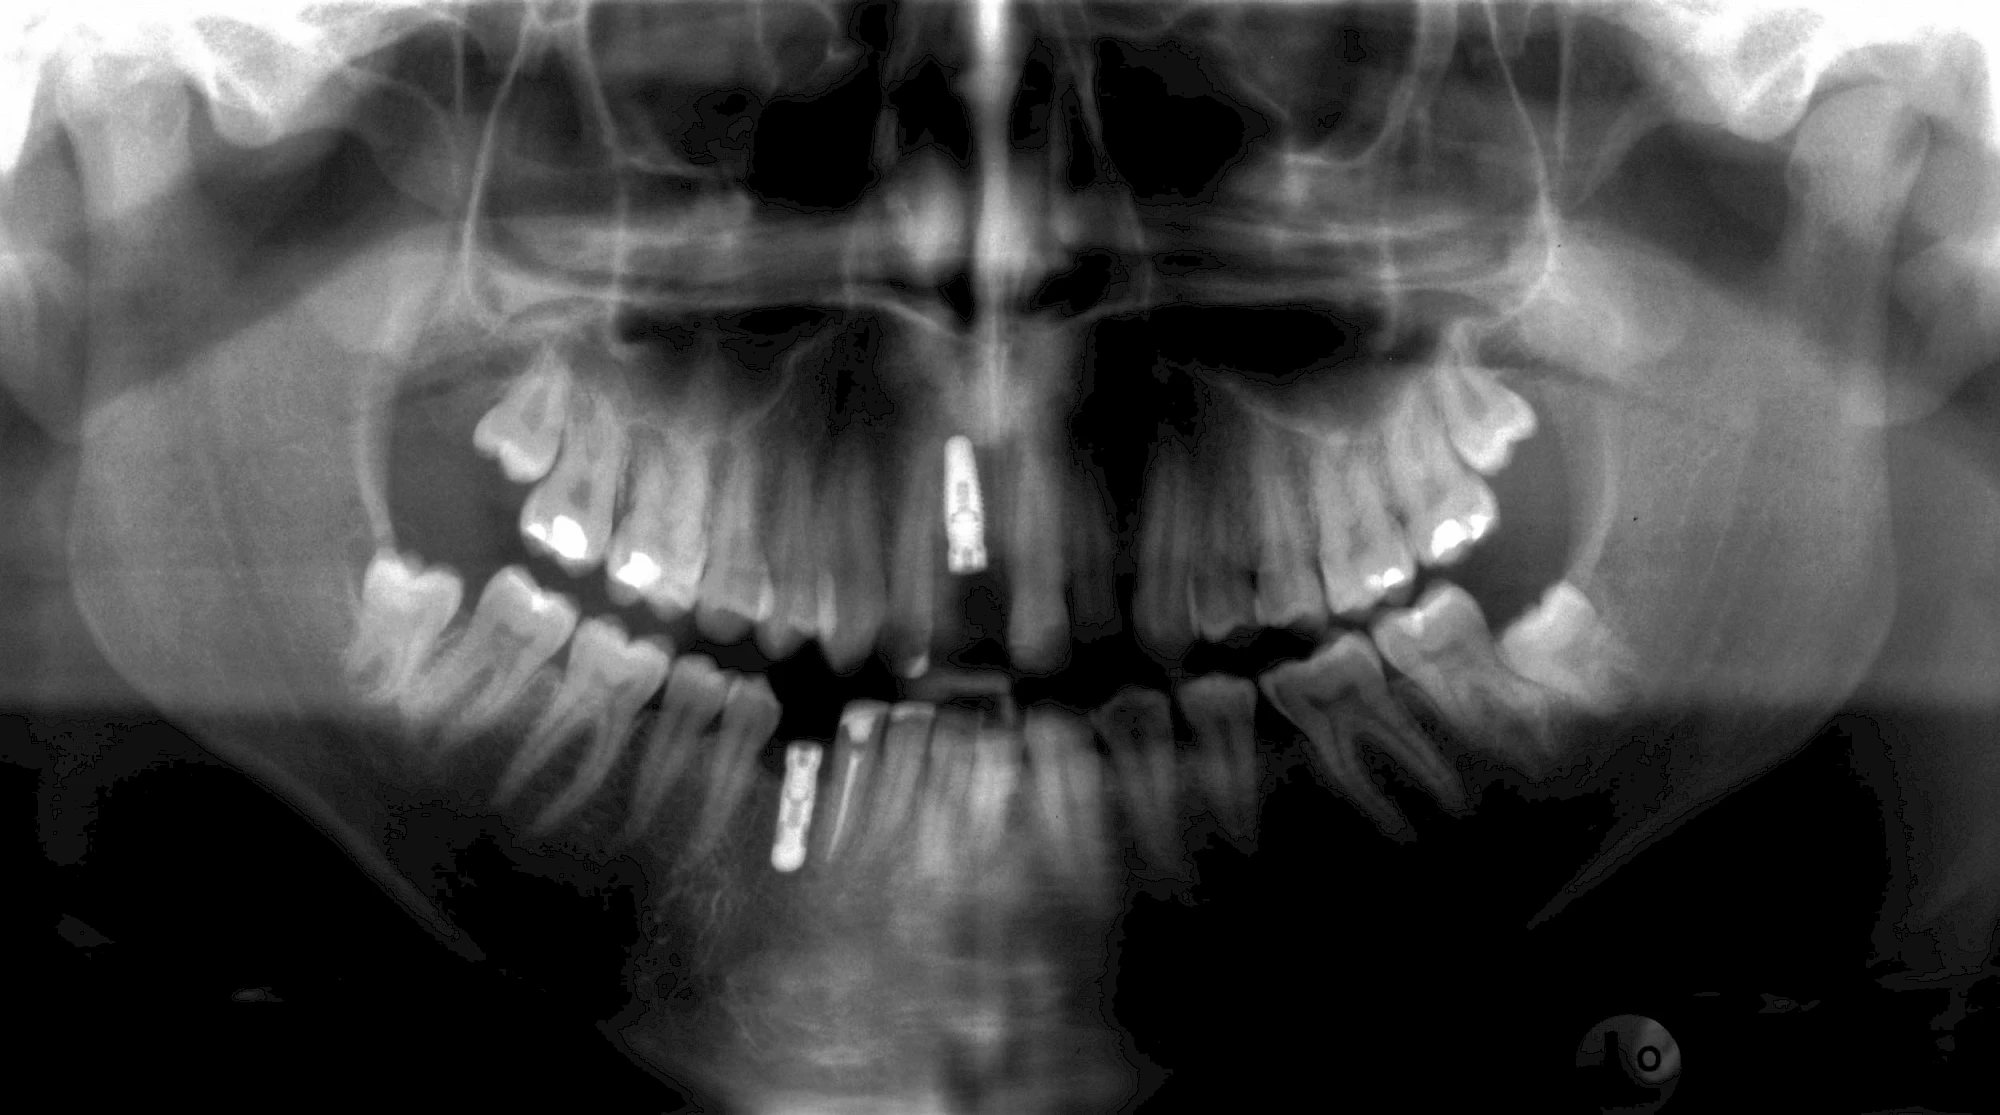

Implantatplanung

Damit Implantate an der richtigen Stelle im Kieferknochen platziert werden könen, gibt es heute vielfältige Möglichkeiten der Planung. In vielen Situationen kann die Erfahrung des Zahnarztes ausreichend sein.

Nicht selten ist jedoch auch eine technisch aufwändigere Vermessung im Vorfeld sinnvoll, z. B.:

- Wenn sich der Kieferknochen abgebaut hat

- Wenn der Nervverlauf im Unterkiefer beachtet werden muss

- Wenn die Ausdehung der Kieferhöhle im Oberkiefer beachtet werden muss

- Wenn wenige Restzähne keine gute Orientierung erlauben

In diesen Fällen kann die Planung mittels verschieden aufwendiger Röntgen-Techniken (Übersichtsaufnahme, DVT) ggf. unter Zuhilfenahme speziell angefertigter Planungsschablonen sinnvoll sein.